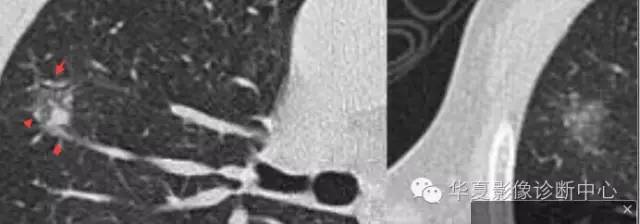

大家仔细看看这个中央不强化的腔内壁

你会发现内壁强化明显,边界清楚

一般这是炎性的脓腔,内层是肉芽肿,明显强化,分界清楚

癌肿的坏死一般是缺血性的,是肿瘤生长速度过快,中央带的血管受挤压,中央供血不足坏死的,一般边界模糊

内有内层强化,不会这么清楚

这是两者坏死的差异

内带强化带,边界清楚

但是这个其实整体看起来不是分叶征

只是一个一个的凸起